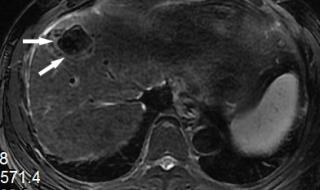

原发性肝癌,又叫肝癌,是肝脏细胞或肝内胆管上皮细胞发现的恶性肿瘤。肝脏发现肿瘤,可以是肝脏本身产生的,也可以是其他部位转移而来的。如果比如胃癌转移到肝脏,叫胃癌肝转移。原发性肝癌在我们最常见的是慢性肝炎导致肝硬化,发展成原发性肝癌。

原发性肝癌发展到了晚期的话会出现一些恶液质状态,比如患者的肚子会出现非常鼓的现象,并且伴随有腹胀的感觉,还会出现黄疸的现象,体质状况会越来越虚弱,这个时候的治疗主要是是保守治疗为主,还有进行化疗或者是介入治疗等综合治疗的措施。